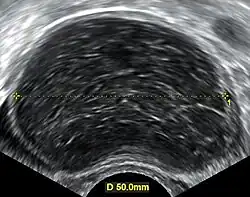

Further work up involves imaging, such as a pelvic ultrasound or CT scan.[7] Theca lutein cysts with diameters over 6 cm in size can be seen through these imaging modalities.[18] Benign ovarian cysts and complex cysts that are potentially malignant are distinguishable via ultrasounds.[19] Labs are also collected to evaluate leukocytes and tumor markers, such as beta-hCG and cancer antigen 125 (CA125).[20]

During pregnancy, ultrasonography is the first-line method for evaluating ovarian cysts. Both transabdominal and transvaginal route of ultrasonography are used with either two-dimensional or three-dimensional modalities.[3] Two-dimensional is more common, but three-dimensional can offer more results.[3] Doppler ultrasonography can also be used and is helpful at analyzing the characteristics of the cyst.[3] It can identify the presence of color flow within a septum as well as the presence of a solid component of the mass.[3] Ultrasonography is an effective tool for observing the progression or regression of the cyst.[3] Magnetic resonance imaging (MRI) is the second-line method used when ultrasonography cannot detect the cyst.[3] Cysts that are too large to be accurately analyzed by ultrasonography are typically when MRI would be used.[3] The advantages of MRI are its larger field of view and multiplanar capabilities.[21] In addition, pathologies such as infarctions and placental invasive disorders can be seen more clearly.[3] MRI is especially beneficial in gestational age and obese people.[3] MRI is also beneficial at preventing the exposure of ionizing radiation to the fetus during pregnancy.[22] Both ultrasonography and MRI show enlarged ovaries with multiple theca lutein cysts.[3]